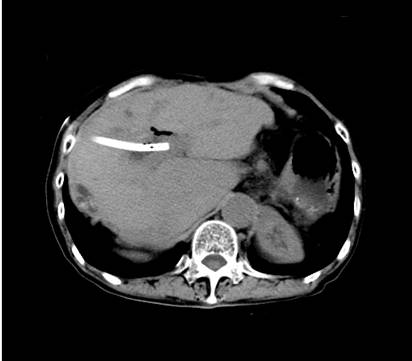

经过二次经皮经肝胆道镜碎石取石术(PTCSL),术后二月复查CT提示肝内胆管结石被取尽